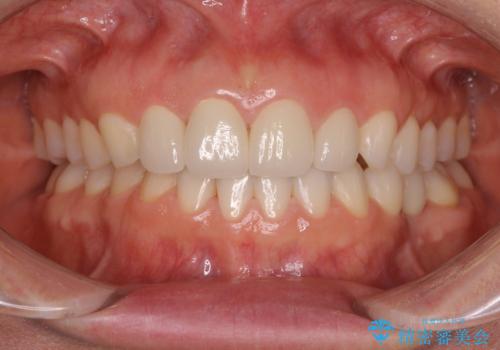

前歯を綺麗にしたい 部分矯正とセラミック治療

- 大きすぎる上顎前歯と、隙間の空いた下顎歯列を気にして来院された患者様です。

上顎前歯にはセラミッククラウンが装着されており、顔や他の歯と比較して幅の大きい状態でした。

下顎前歯は空隙歯列弓であったので、アンカースクリューとワイヤー装置を用いてスペースを閉じていくこととし、上顎前歯は矯正治療用の仮歯に置き換えた上で、仮歯の大きさを削って小さくしながら、上下前歯部の部分矯正を行うこととしました。

矯正治療後は、仮歯とした上顎前歯をオールセラミッククラウンにて補綴治療を行うこととしました。

日本と海外を拠点に仕事をされていらっしゃるため、数ヶ月治療があいてしまうことがあり、期間はかかりましたが、2年間で望み通りの前歯に仕上げることができました。